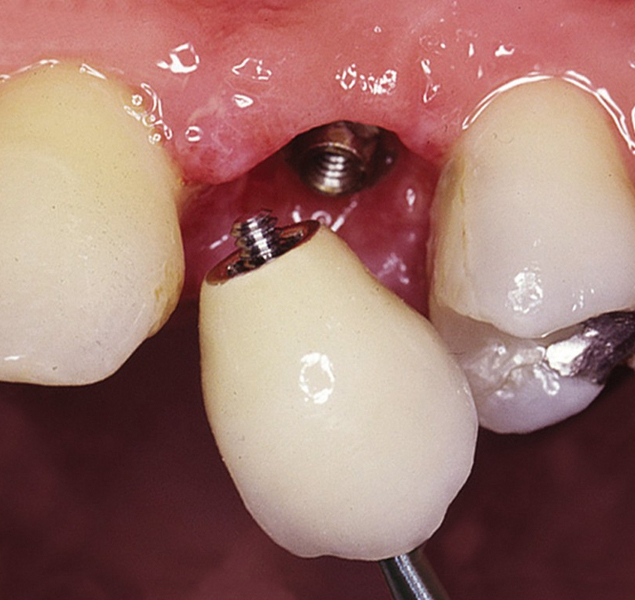

Protetické řešení může být pomocí můstku, který je kotvený na implantátech nebo pomocí jednotlivých korunek na implantátech.

V zásadě je možné do těchto můstků zařadit i přirozené zuby, zejména pokud je potřeba tyto zuby ošetřit proteticky

- korunkami. Korunky nebo můstky mohou být na implantáty nacementovány nebo přišroubovány.